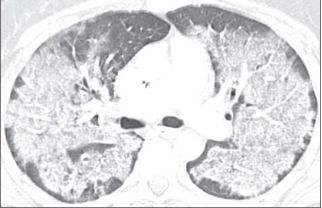

下图是非常典型的蝶翼征。

再来一个更直白的蝶翼征,几乎可以翩翩起舞了。